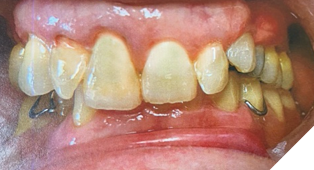

A 72-year-old Caucasian female presented with long-standing TMJ discomfort and missing teeth. She was diagnosed with partial mandibular edentulism (missing 37, 45, 46, 47), generalized attrition, and arthrogenic TMD due to posterior bite collapse. Her periodontal condition was stable.

After informed consent, Phase I began with delivery of a Gelb appliance (Fig. 3ABC), which was adjusted periodically until achieving the treatment VDO. Phase II involved stabilization at this VDO. Teeth 36, 35, 43, and 44 were prepared simultaneously, and impressions (Henry Schein VP MIX) and bite registration (Kopy ultra-fast VPS) were taken using the palatal jig.